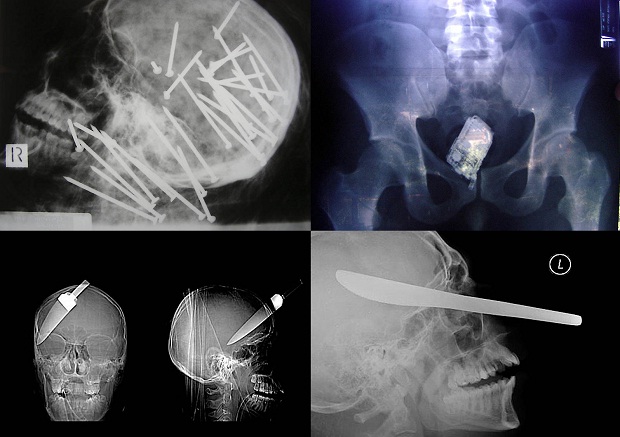

1. Cамые странные рентгеновские снимки.